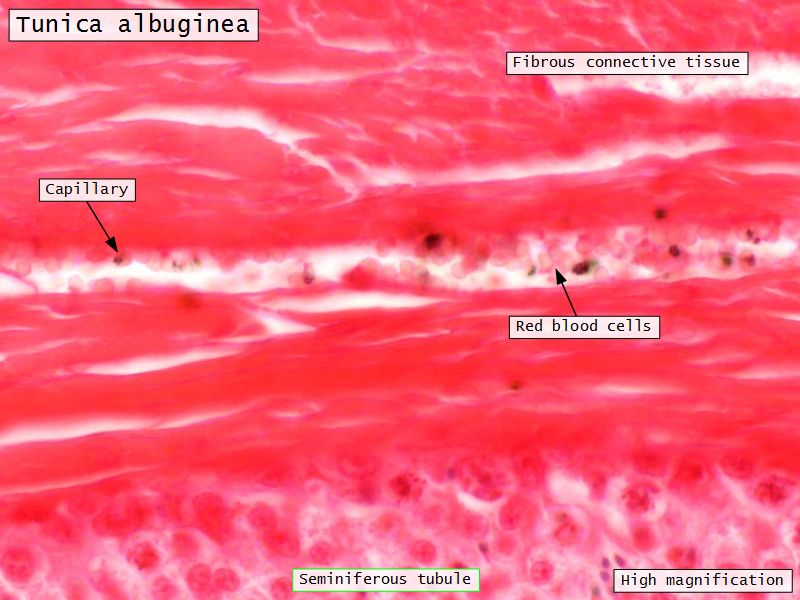

Tunica albuginea

- Thick fibrous CT capsule

- Forms septae

- Divide testis into lobuli